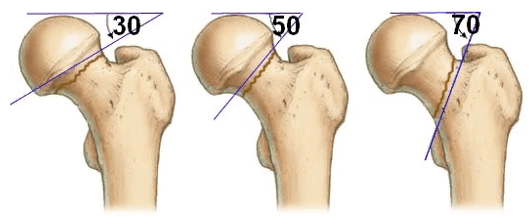

В структуре травм проксимальной зоны бедренной кости по типу перелома целых 55% составляют поражения шейки, и происходят они преимущественно на фоне возрастного остеопороза. Для сравнения, примерно в 40% случаев страдает целостность вертельной части и всего в 5% - подвертельная область. ПШБ является внутрисуставным, а потому требует безотлагательного раннего лечения. Он в 99,99% не может зажить самостоятельно, без высокоточной репозиции, что почти всегда служит поводом для оперативного вмешательства. Абсолютными показаниями к операционной репозиции являются:

- выявленные смещения костных отломков бедра, даже незначительные;

- наличие оскольчатого вида перелома (определяется более 2 осколков);

- разлом по вертикальной линии;

- комбинированная форма травмы, например, в сочетании с вывихом;